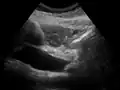

On abdominal ultrasonography, the common bile duct is most readily seen in the porta hepatis (where the CBD lies anterior to the portal vein and hepatic artery). The absence of Doppler signal distinguishes it from the portal vein and hepatic artery.

-

Borderline of a dilated perihilar bile duct, measuring 8 mm. -

Dilatation of CBD due to an ampullary tumor.